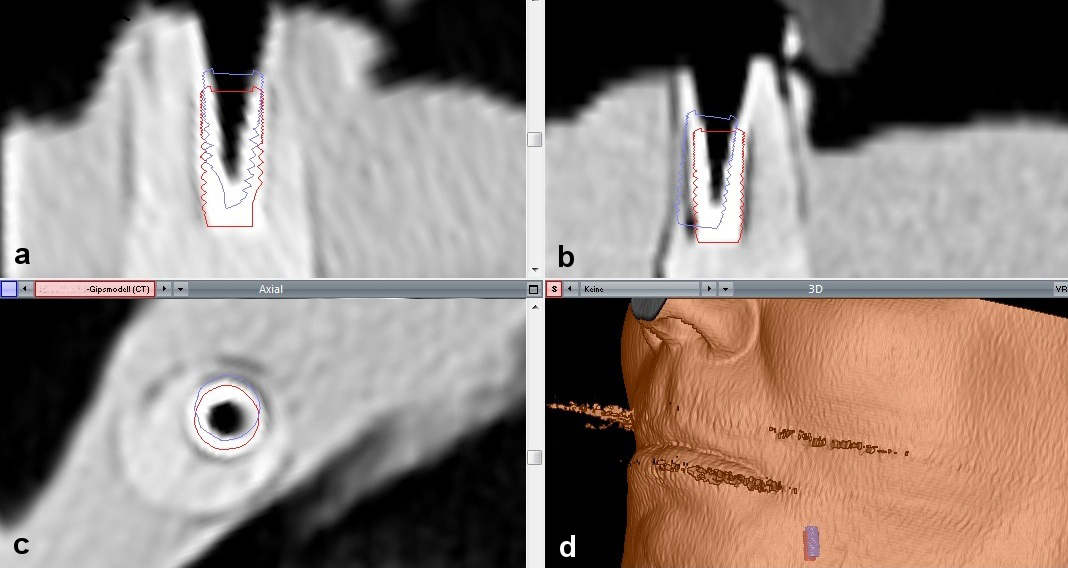

Following software-based automatic image fusion, a virtual implant with the same dimensions as the clinically placed implant was positioned manually on the implant shown on the CT scan. This implant was highlighted by red contour lines. An assessment of implant position was possible in all planes. The originally planned implant was shown by blue contour lines (Figure 10 [Fig. 10]).

Figure 10: Screenshot after automatic image fusion of preoperative planning and a postoperative CT of the cast with an implant analogue (Voxim skeleton module, IVS Solutions AG, Chemnitz, Germany) a) saggital view; b) coronal view; c) axial view; e) 3D The virtual implant that was manually fused with the implant shown on the CT scan is represented by red contour lines. These red lines show the actual position of the implant. The blue contour lines show the planned position of the implant. The figure presents a case with deviations above average for illustration reasons.